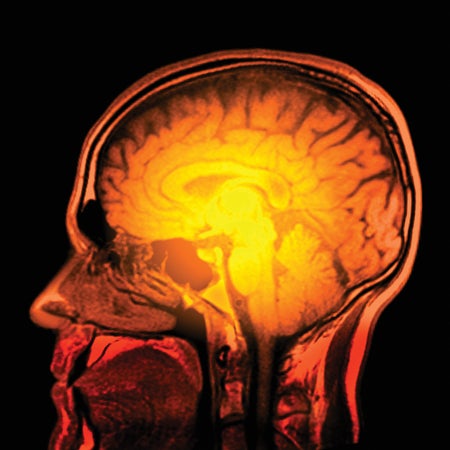

Device Decodes ‘Internal Speech’ in the Brain

Technology that enables researchers to interpret brain signals could one day allow people to talk using only their thoughts

A Cubic Millimeter of a Human Brain Has Been Mapped in Spectacular Detail

Google scientists have modeled all 150 million connections of a fragment of the human brain at nanoscale resolution

Scientists Discover Extensive Brain-Wave Patterns

Certain brain layers specialize in particular waves—which might aid understanding of neuropsychiatric disorders